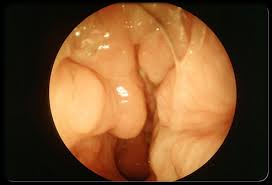

Anatomy of the sinuses (also called paranasal sinuses): The human skull contains four major pairs of hollow air-filled-cavities called sinuses. These are connected to the space between the nostrils and the nasal passage. Sinuses help insulate the skull, reduce its weight, and allow the voice to resonate within it. The four major pairs of sinuses are the:

• frontal sinuses (in the forehead),

• maxillary sinuses (behind the cheek bones),

• ethmoid sinuses (between the eyes), and

• sphenoid sinuses (behind the eyes).